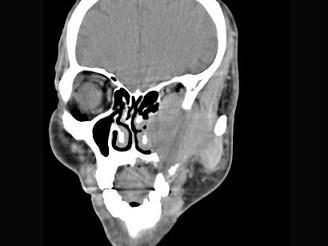

问题 男,65岁,左眼球突出近一年,鼻涕带血,面颊部隆起,同时面颊部有麻木感,CT检查如图,最可能诊断为 ( )

选项 A、上颌窦癌 B、骨肉瘤 C、上颌窦血管瘤 D、上颌窦囊肿 E、上颌窦息肉

答案 A